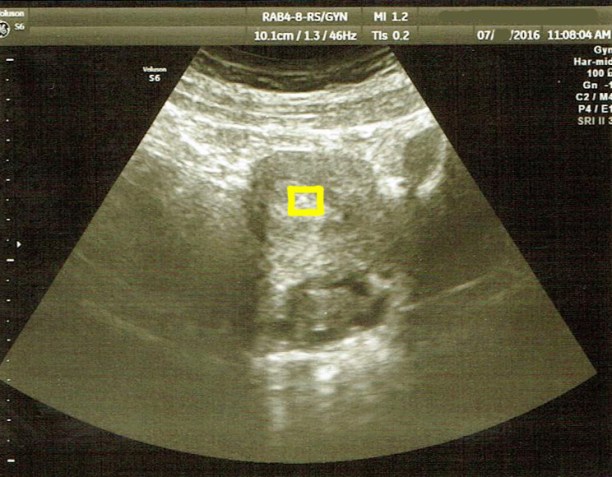

Here are this weeks ultrasound pictures:

Baby B